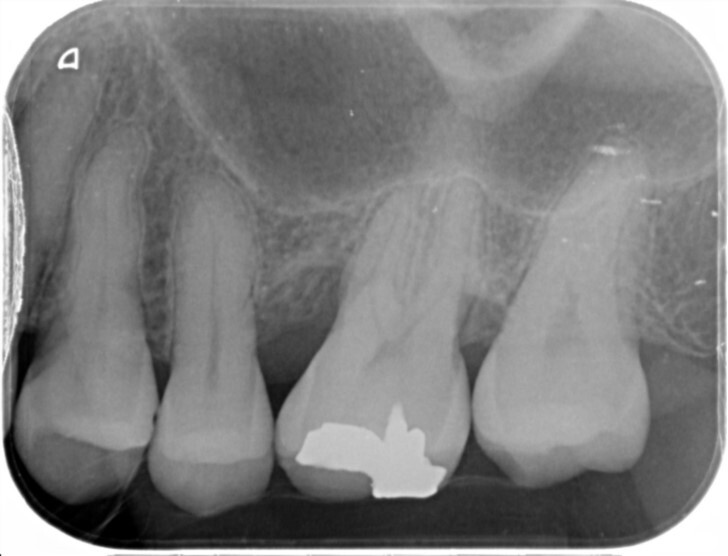

1.歯周組織検査、口腔内写真撮影、X線撮影の実施

現在のお口の状態を正確に把握するため、歯ぐきの検査、口腔内写真やレントゲン撮影を行います。歯周ポケットの深さや歯を支える骨の状態を確認し、歯周病の進行度を詳しく診断します。